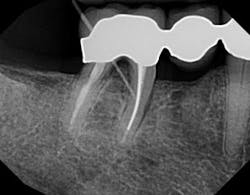

Most fistulas are endodontic or periodontal in nature. The appropriate specialist referral is possible with endodontic gutta percha (GP) points. As they appear radiopaque on x-rays, threading an open fistula can help confirm the origin of its source. Every office should have a vial of 30-gauge GP for this reason. First, break the point in half so that during an x-ray the patient does not accidentally bite down on it. Using cotton pliers, gently guide the point through the fistula until there’s resistance. A radiograph can then be used to determine the next course of action. Don’t be fooled and assume the source. Many times, a GP point will veer off in a surprising direction.

These same GP points can be used as a patient visual for probing depth. How many times have you probed an area of bone loss or potential fracture, only to have the patient respond, “But it’s not bothering me”? GP points can be directed into sulcus spaces and radiographed as a visual.